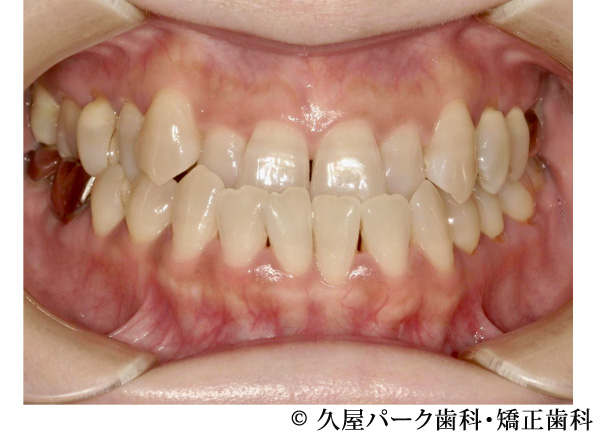

【症例3】叢生(歯のでこぼこ)の症例

- 治療前

- 治療後

- 治療名

- 叢生(歯のでこぼこ)の症例

- 費用

- 660,000円(税込)

※矯正相談・精密検査・オーダーメイド治療計画の費用はいただいておりません - 期間

- 2年4ヵ月

- 通院

- 1ヵ月ごと

- 性別・年代

- 女性・20代

治療内容

患者様の症状

全体的にでこぼこが気になるということで当院で治療を開始された患者様です。

治療法

ワイヤー矯正での歯並び改善

上下左右4番抜歯 -

治療結果

でこぼこが改善されました。

※治療結果は個人差があります。

治療を行う上での注意点(リスク・副作用)

・治療の初期段階では、痛みや不快感が生じやすくなりますが、一週間前後で慣れます

・歯の動き方には個人差があるため、予想された治療期間より延長する場合があります